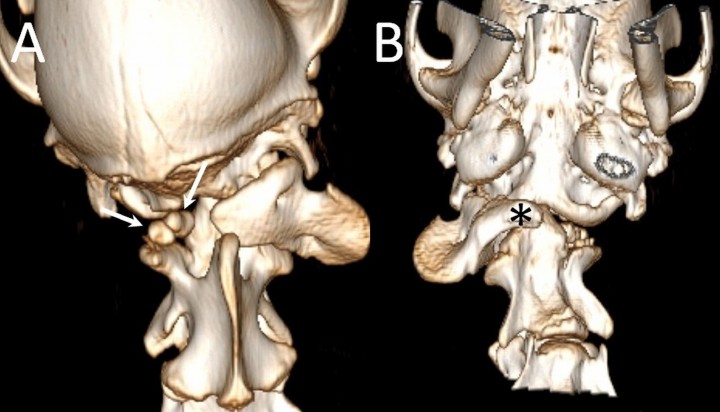

Es referida para evaluación neurológica una perra mestiza de 4 meses de edad y 23 kilos de peso por presentar dolor cervical y tetraparesia de 4 días de evolución tras sufrir un traumatismo. En la exploración física se palpó una asimetría del atlas, que parecía rotado, lo que hacía que el paciente sufriese una desviación severa del cuello con gran dolor a la manipulación. El examen neurológico reveló tetraparesia ambulatoria severa con retraso simétrico de las reacciones posturales en las cuatro extremidades. Los reflejos medulares y la evaluación de los pares craneales eran normales. Este examen fue compatible con una afección focal o difusa de los segmentos medulares C1 - C5. El diagnóstico diferencial, teniendo en cuenta la historia clínica y la exploración física, incluyó principalmente procesos de carácter malformativo, sin poder descartarse enfermedades traumáticas, inflamatorias o neoplásicas. Se realizaron radiografías de la columna cervical en proyección lateral y ventrodorsal donde se apreció una inestabilidad de la articulación AA evidenciada por aumento de distancia entre la lámina del atlas y la apófisis espinosa del axis (Fig. 1A). Sin embargo, el hallazgo más relevante consistió en la ausencia del ala (apófisis transversa modificada) y la mitad izquierda del cuerpo del atlas (Fig. 1B). Posteriormente se procedió a la realización de una tomografía computarizada (TC) donde se confirmó la existencia de una malformación cervical con desplazamiento rostral del axis, que hacía que el diente del axis sobrepasase el límite craneal del cuerpo del atlas y los cóndilos del occipital, quedando en contacto con el aspecto ventral de la médula oblonga (signo radiológico denominado “invaginación basilar” en medicina humana) (Fig. 2, A y B). El atlas presentaba una agenesia de su mitad izquierda y en su lugar se apreciaron dos pequeños núcleos óseos independientes que ocupaban una posición dorsolateral izquierda no unidos con el resto de estructuras óseas (Fig. 2, C). Aunque el arco derecho del atlas quedaba íntimamente asociado con el cóndilo derecho del occipital, se evidenció una conformación atlanto-occipital derecha normal, con una línea articular bien formada pero rotada (Fig. 2, B). En el aspecto ventral del atlas se observaba el “intercentrum” 1, así como la sincondrosis neurocentral derecha (Fig. 2, B). Sin embargo, la sincondrosis neurocentral izquierda y la dorsal no podían ser evidenciadas debido a la ausencia del centro de osificación del arco neural izquierdo (Fig. 2, C). Todas estas alteraciones hacían que la articulación atlanto-occipital quedase rotada, haciendo que la cabeza girase en contra del sentido de las agujas del reloj visto desde un plano dorsal (Fig. 3, A y B). El agujero vertebral lateral y el agujero transverso del arco derecho del atlas estaban correctamente formados (Fig. 3, A). Por otro lado, se apreció como el aspecto craneal del cuerpo del axis y la apófisis odontoides estaban deformados, engrosados e hiperostóticos (Fig. 2, A). El borde craneal de la apófisis espinosa del axis quedaba deformado con desviación derecha, haciendo leve prominencia sobre el atlas (Figs. 2A y 3A). Posteriormente, se decidió realizar una resonancia magnética de la columna cervical para valorar el parénquima medular, donde se evidenció una severa compresión dorsoventral de la médula espinal a nivel de la articulación AA con obliteración del espacio subaracnoideo ventral y dorsal (Fig. 4). Las secuencias ponderadas en T2 demostraron la hiperintensidad del parénquima medular en el punto de mayor compromiso (Fig. 4).

<p><strong>(A) </strong>Reconstrucción sagital obtenida mediante TC de la unión craneocervical. Obsérvese el desplazamiento craneal del axis sobre el cuerpo del atlas que hace que el diente deformado y engrosado sobrepase el hueso basioccipital desplazando a la médula oblonga (flecha), denominado invaginación basilar. <strong>(B)</strong> Imagen transversal obtenida mediante TC a nivel de los cóndilos del occipital en la que se puede apreciar como el diente del axis está incluido dentro de la cavidad craneal (flecha) y la adecuada formación de los cóndilos del occipital (asteriscos). Tambien puede apreciarse el intercentrum I (cruz) y la sincondrosis neurocentral derecha (punta de flecha), pero no la izquierda. En esta imagen la rotación del atlas es evidente teniendo en cuenta la posición del cuerpo (flecha circular que indica el sentido de la rotación). <strong>(C) </strong>Imagen transversal obtenida mediante TC a nivel de la lámina del atlas en la que se aprecian dos núcleos de osificación independientes de posición dorsolateral izquierda (puntas de flecha).</p>

Figura 2

(A) Reconstrucción sagital obtenida mediante TC de la unión craneocervical. Obsérvese el desplazamiento craneal del axis sobre el cuerpo del atlas que hace que el diente deformado y engrosado sobrepase el hueso basioccipital desplazando a la médula oblonga (flecha), denominado invaginación basilar. (B) Imagen transversal obtenida mediante TC a nivel de los cóndilos del occipital en la que se puede apreciar como el diente del axis está incluido dentro de la cavidad craneal (flecha) y la adecuada formación de los cóndilos del occipital (asteriscos). Tambien puede apreciarse el intercentrum I (cruz) y la sincondrosis neurocentral derecha (punta de flecha), pero no la izquierda. En esta imagen la rotación del atlas es evidente teniendo en cuenta la posición del cuerpo (flecha circular que indica el sentido de la rotación). (C) Imagen transversal obtenida mediante TC a nivel de la lámina del atlas en la que se aprecian dos núcleos de osificación independientes de posición dorsolateral izquierda (puntas de flecha).

<p><strong>(A)</strong> Reconstrucción tridimensional en vista dorsal obtenida mediante TC. Obsérvese la rotación de la cabeza con respecto al eje longitudinal y la ausencia de la totalidad del arco izquierdo del atlas, donde solo es posible apreciar dos pequeños fragmentos óseos (flechas). <strong>(B) </strong>Reconstrucción tridimensional en vista ventral obtenida mediante TC en la que se aprecia el “intercentrum 1” rotado (asterisco), así como la ausencia del arco izquierdo del atlas. El defecto de la cavidad timpánica izquierda es un artefacto creado durante la reconstrucción.</p>

Figura 3

(A) Reconstrucción tridimensional en vista dorsal obtenida mediante TC. Obsérvese la rotación de la cabeza con respecto al eje longitudinal y la ausencia de la totalidad del arco izquierdo del atlas, donde solo es posible apreciar dos pequeños fragmentos óseos (flechas). (B) Reconstrucción tridimensional en vista ventral obtenida mediante TC en la que se aprecia el “intercentrum 1” rotado (asterisco), así como la ausencia del arco izquierdo del atlas. El defecto de la cavidad timpánica izquierda es un artefacto creado durante la reconstrucción.